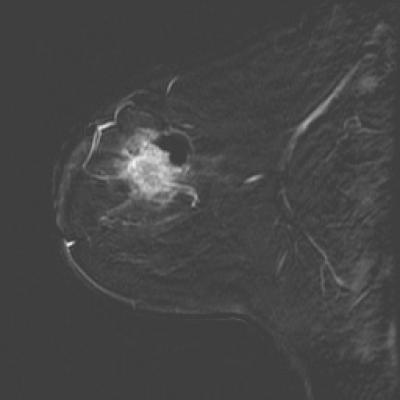

Microwave imaging can be used to monitor how well treatment for breast cancer is working, finds new research published in BioMed Central's open access journal Breast Cancer Research . Microwave tomography was able to distinguish between breast cancer, benign growths, and normal tissue.

Eight women with breast cancer were treated with chemotherapy until surgery, as part of their normal therapy. During treatment, magnetic resonance image was supplemented with microwave tomography at the Dartmouth-Hitchcock Medical Center. Regions of high conductivity corresponded to the tumors, low conductivity to normal tissues, and unlike other imaging techniques, body mass index (indicating the amount of body fat), age or breast density did not appear to affect the results.

This imaging technique is low cost and can be repeated at numerous stages during treatment. Paul Meaney from Dartmouth College, who led the study explained, "By recalling patients for scans during their treatment we found that we could actually see tumors shrinking in women who responded to chemotherapy. Microwave tomography could therefore be used to identify women who are not responding to initial therapy and their treatment changed appropriately at an early stage."